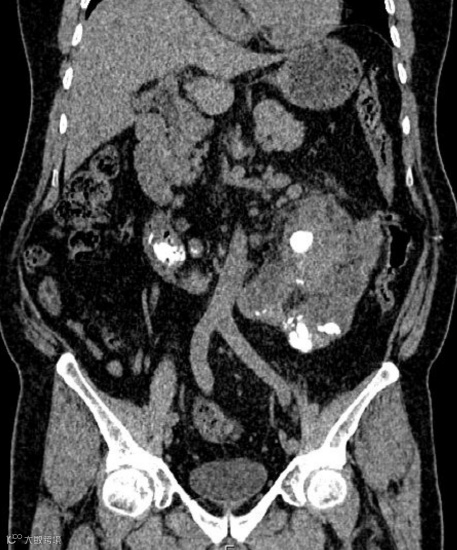

女,25岁,马蹄肾。肾脏下极相连,呈马蹄形,肾皮质厚度正常,泌尿系统未见梗阻扩张。